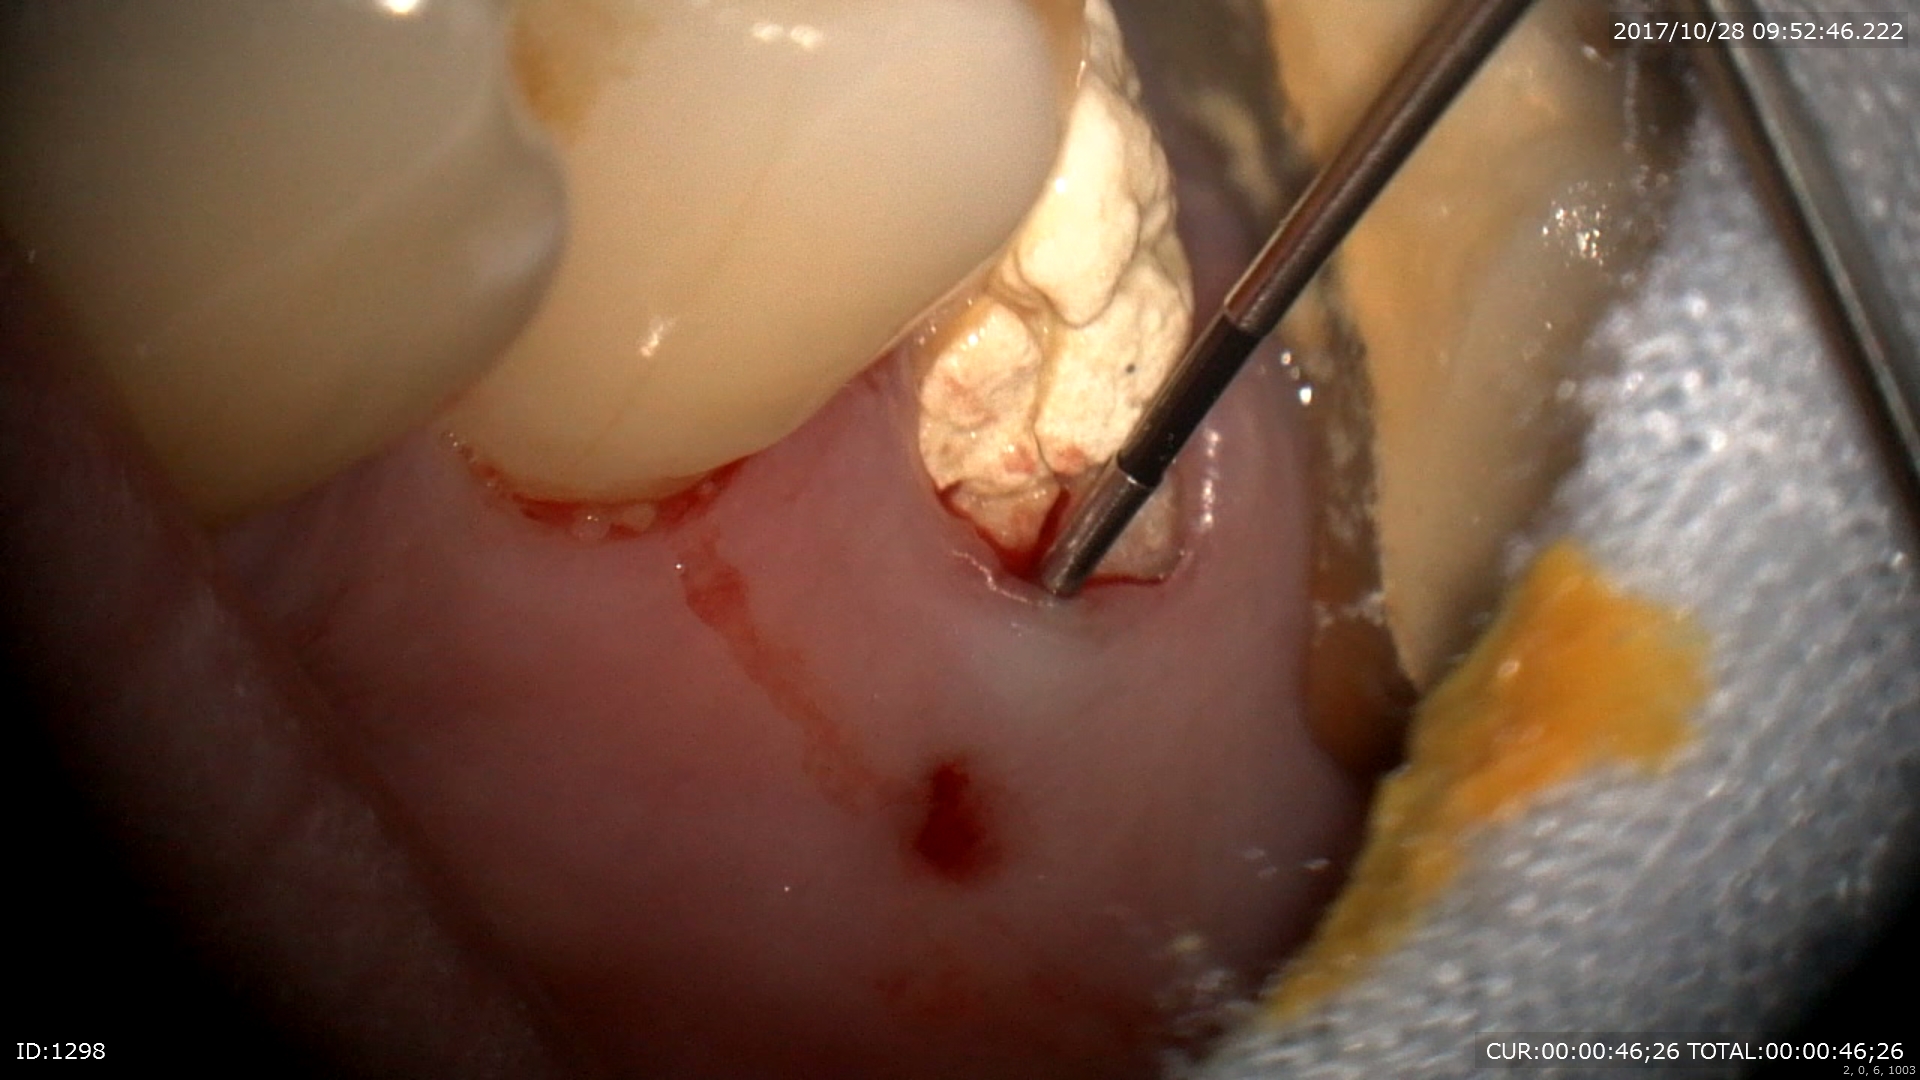

赤い跡が歯茎にありますよね。これは膿の出口にあたります。この様な時に「診断」が大切になります。CTとマイクロスコープによってこの歯はハセツと診断されました。

ポケットは9mm。

マイクロスコープだと割れているラインが見えますね。